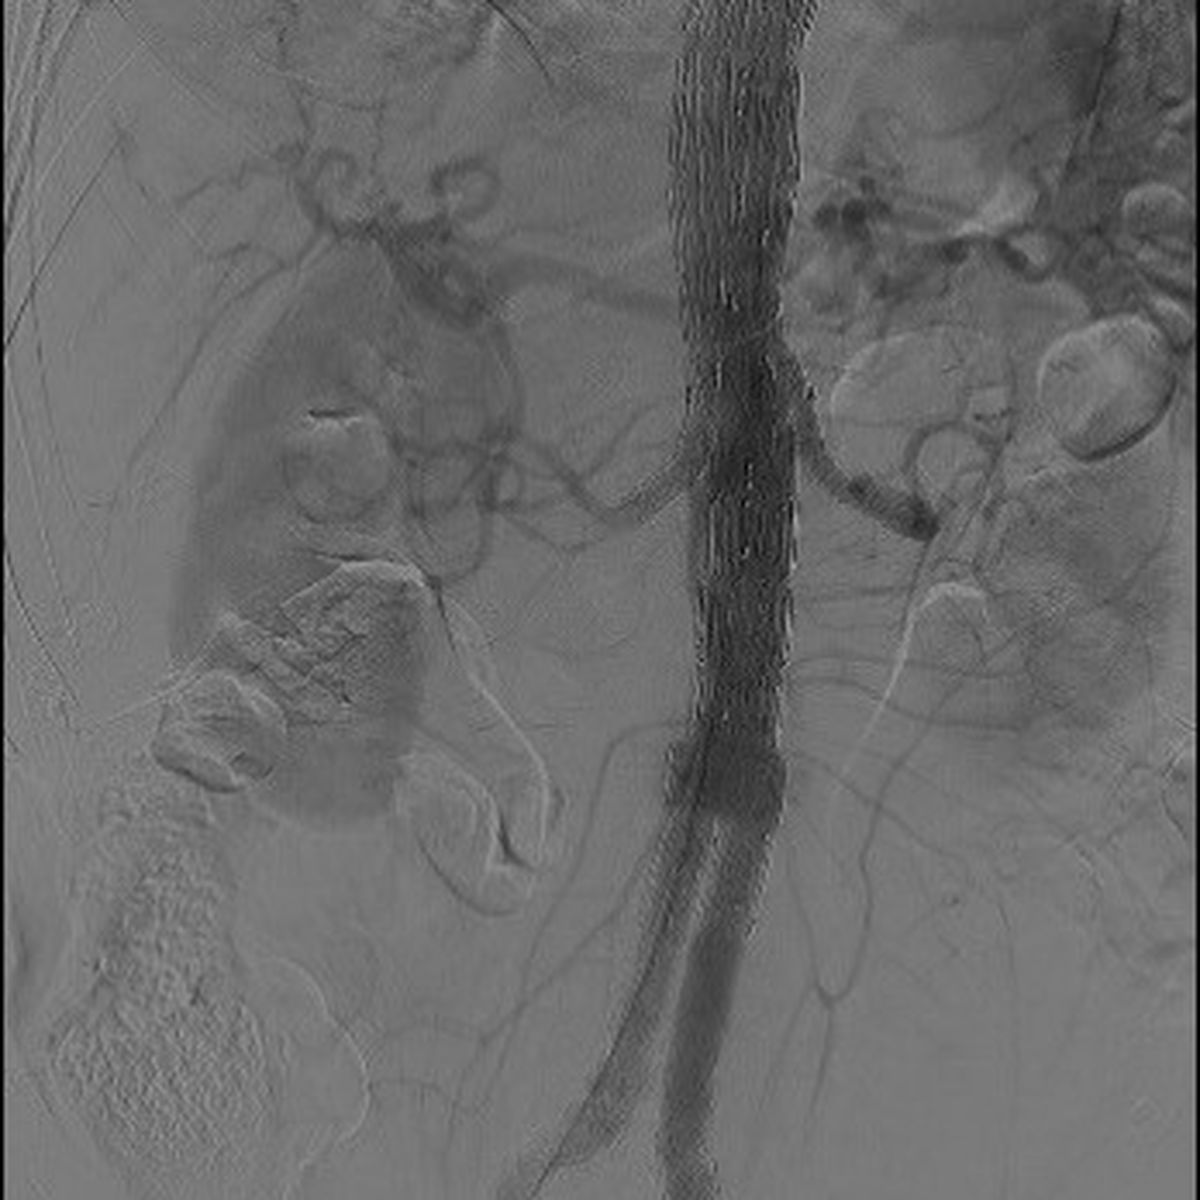

L’endoprothèse a révolutionné le traitement des anévrysmes aortiques : au lieu de pratiquer un geste chirurgical enlevant l’anévrysme, il s’agit d’exclure celui-ci en posant un stent, qui l’élimine de la circulation sanguine générale. Cette pose est effectuée par voie endovasculaire, avec un risque de mortalité nettement plus faible que celui de la chirurgie. Néanmoins, cette technique impose une surveillance à vie des patients pour repérer l’apparition d’éventuelles complications comportant un risque de rupture de l’anévrysme (endofuites, migration de la prothèse, perméabilité ou déformation du squelette métallique, plicatures, présence d’anévrismes au-dessus ou en dessous de la zone traitée, etc).

Le plus souvent, cette surveillance est effectuée par scanner, évaluant plusieurs paramètres, comme le diamètre de l’aorte ou la présence de fuites. L’équipe du Pr Michel Alain Bartoli (Hôpital Marie Lannelongue, Marseille – groupe Hospitalier Paris Saint-Joseph) et la société INCEPTO ont développé une solution d’intelligence artificielle (ARVA) qui fournit des mesures automatiques du diamètre anévrysmal en scanner. La solution a été développée pour fournir des mesures du diamètre de l’aorte dans la totalité de son trajet, avec reconstitution 3D. L’énorme avantage de cette technique est de pouvoir comparer les images au fil du temps.